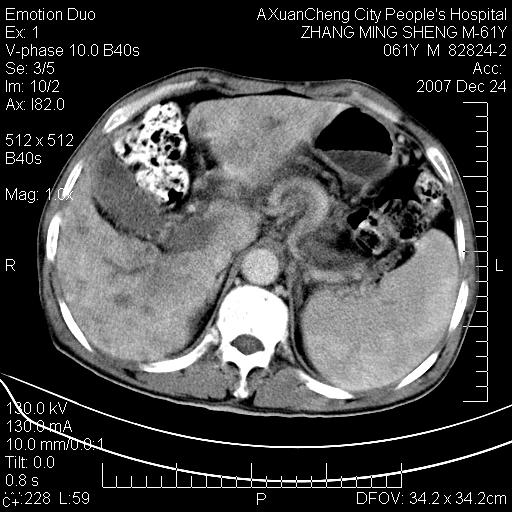

标题: CT11031:M61Y,胰腺占位

大家侃侃门静脉和胆管系统怎么回事,肝内转移?

胰腺癌肝转移

肝硬化,门脉高压,脾肿大;弥漫性肝癌,肝内、门脉、腹膜后淋巴结转移,肝内外胆管扩张,胰头区占位,建议mr检查

胰腺癌伴肝内转移;门脉、肠系膜上v癌栓形成。

考虑为:胰腺癌伴肝脏转移、腹膜后淋巴结转移,门静脉及肠系膜上静脉瘤栓形成。

胰体尾癌伴肝内转移,门静脉及肠系膜上静脉瘤栓形成.